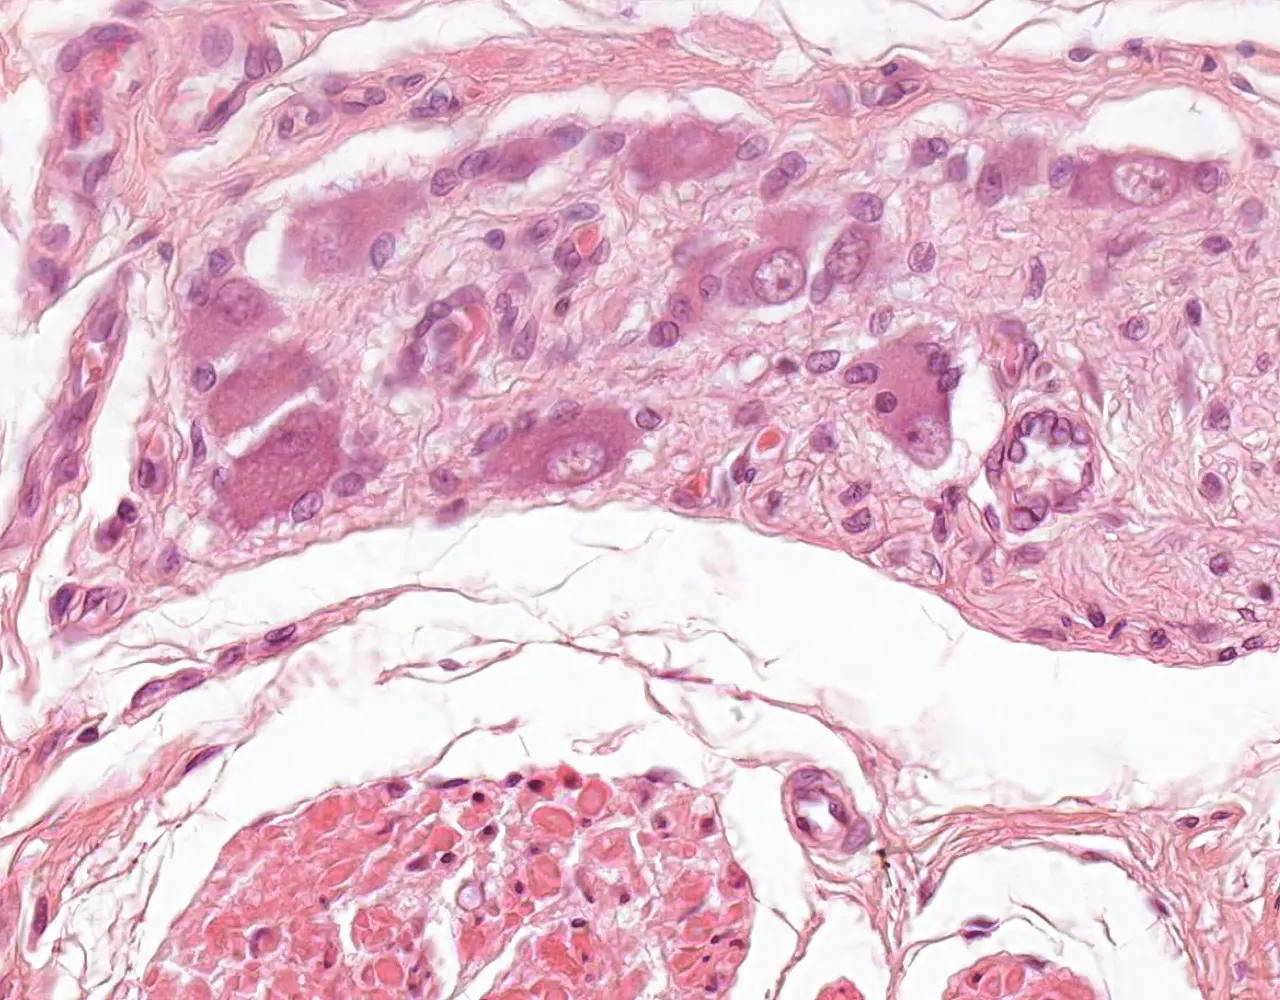

- Microscopically, the esophagus is composed of four layers: mucosa, submucosa, muscularis propria, and adventitia.